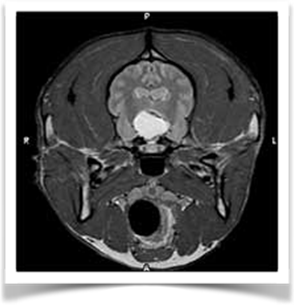

- Malformazioni (idrocefalo, lissencefalia, idrancefalia, displasia corticale…)

- Risonanza magnetica: è l’esame di diagnostica per immagini più affidabile per il riconoscimento di patologie prosencefaliche che causano crisi convulsive.